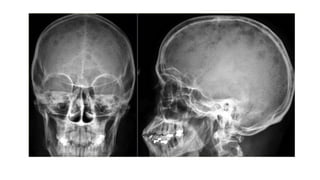

osteoma

🠶An isa benign tumour consisting of dense bone. T

hey

may occur in the paranasal sinuses.

Eosinophil granuloma

🠶 Isthe mildest and most frequent form of Langerhans

histiocytosis.

🠶 It occurs in children and young adults

🠶 Lytic lesions which may be single or multiple, most frequently in

the skull, pelvis, femur and ribs.

🠶 May have the features of an aggressive lesion, or well defined

and may have a sclerotic rim.

🠶A periosteal reaction issometimes seen.